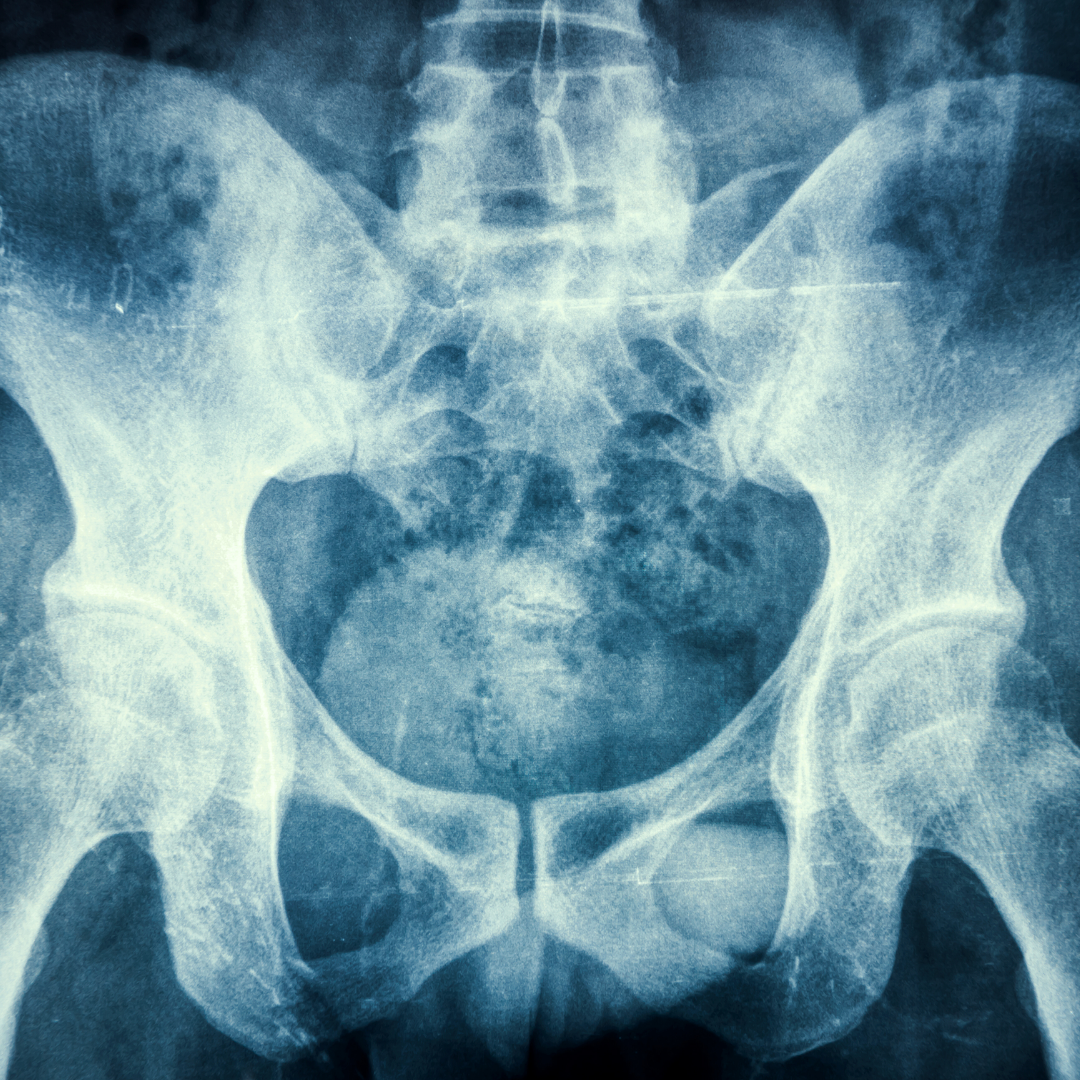

علاج المفصل العجزي الحرقفي

تشخيص اضطراب المفصل العجزي الحرقفي يتطلب تاريخًا شاملاً للمريض وفحصًا جسديًا دقيقًا.

المفصل العجزي الحرقفي يؤدي دورًا حيويًا في امتصاص الصدمات ومنع وصول قوى الصدمة إلى العمود الفقري. أسباب ألم مفصل الحوض الصلب غير معروفة، ولكن هناك عوامل متعددة تؤدي إلى هذا الألم في المفصل، بما في ذلك الصدمات والإصابات.

يمكن أن تشمل أسباب ألم مفصل الحوض الصلب الأخرى ما يلي: